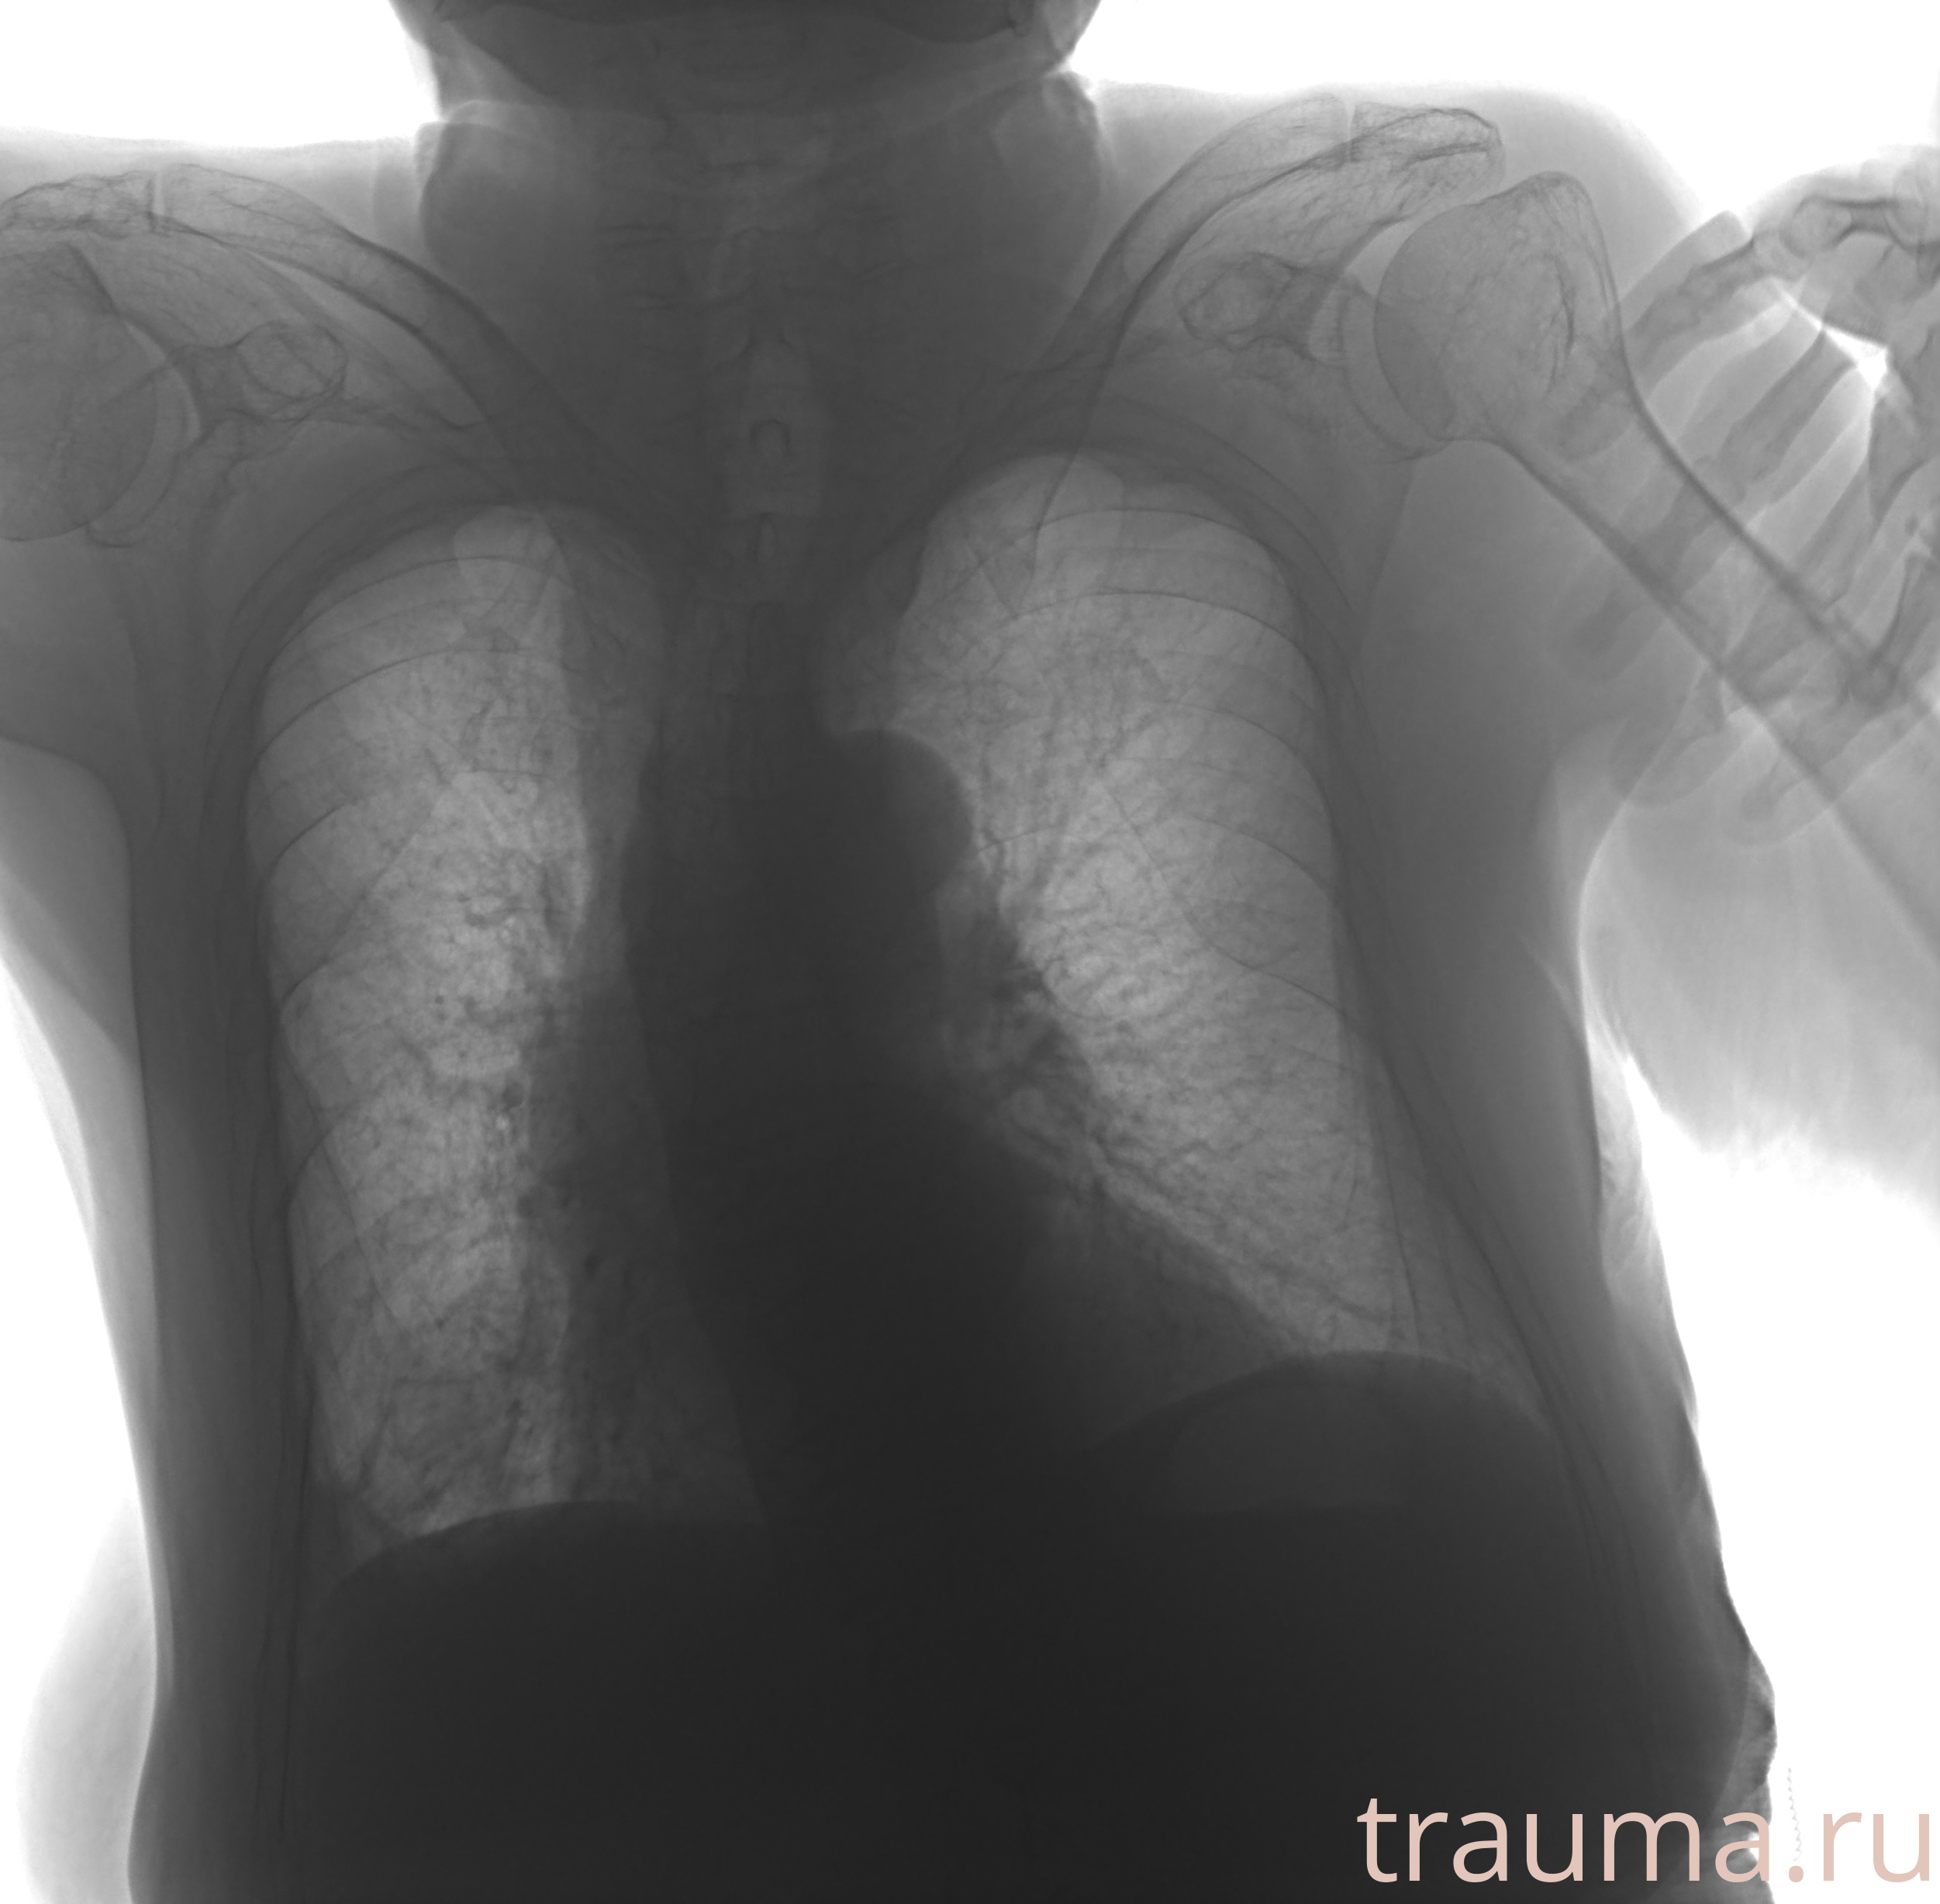

Рентгенограммы

Рентген на дому: по вашему адресу приезжает врач-рентгенолог, травматолог-ортопед с мобильным рентгеновским аппаратом, проводит диагностику травмы или заболевания, делает необходимые рентгенограммы, дает рекомендации по дальнейшему лечению. Получить качественные снимки в домашних условиях возможно благодаря уникальной методике, разработанной МосРентген Центром для института  Склифосовского

при переломе шейки бедра и пневмонии от компании МосРентген Центр - партнера Института имени Склифосовского